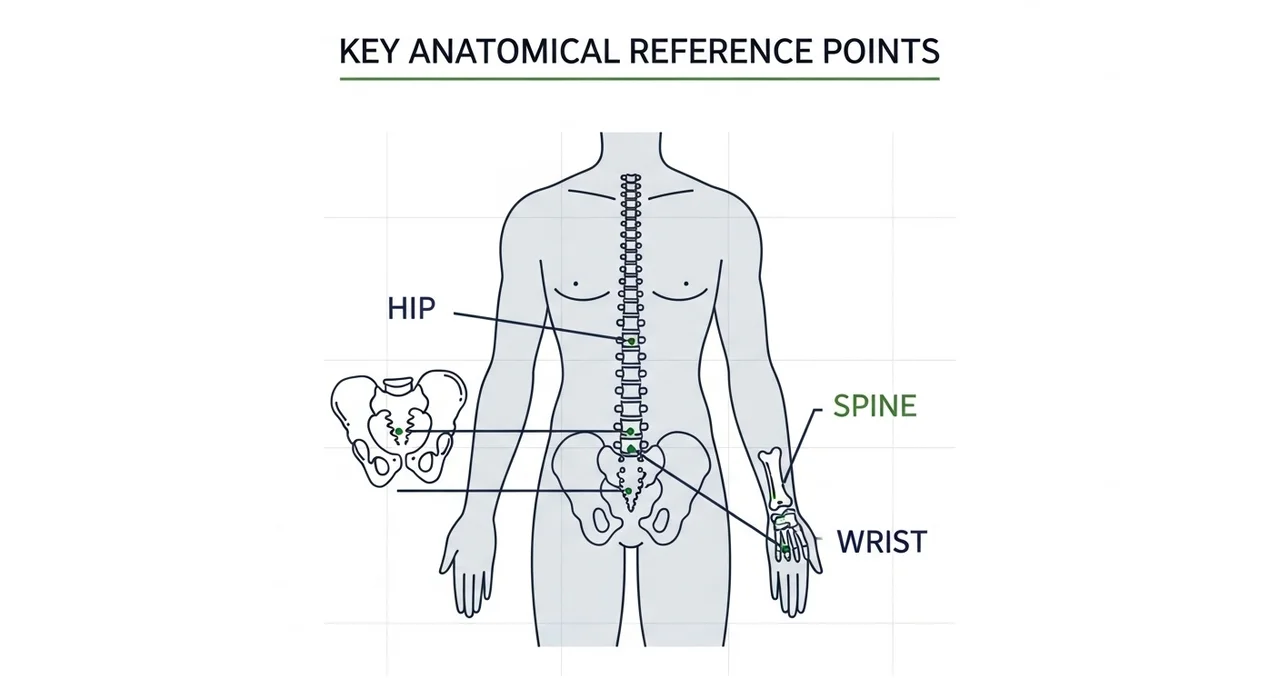

골다공증 골절의 3대 핵심 위험 부위는 고관절, 척추, 손목입니다.

한눈에 보는 골다공증 골절 위험 부위 비교

골다공증으로 인해 골절이 자주 발생하는 부위는 우리 몸의 하중을 견디거나 낙상 시 땅을 짚게 되는 곳들입니다. 각 부위별로 발생하는 연령대와 위험도가 조금씩 달라요. 아래 표를 통해 한눈에 비교해 보세요.